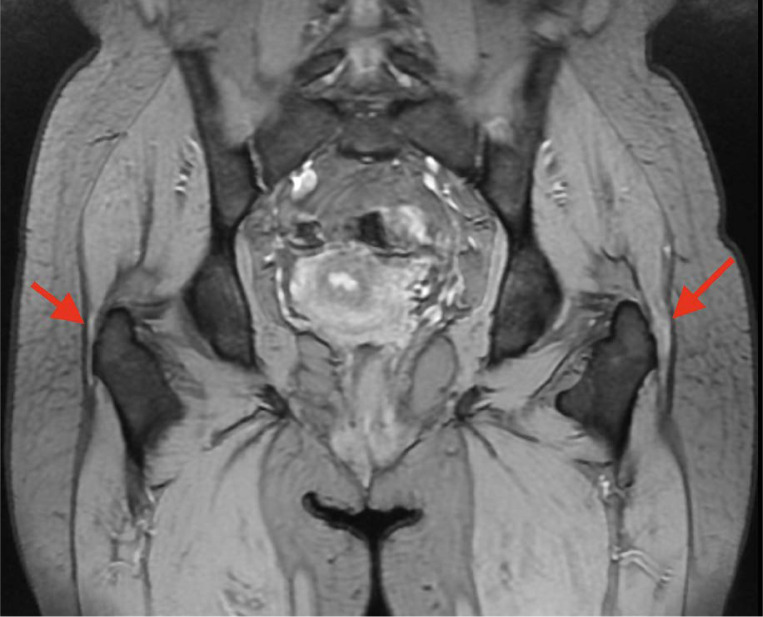

大转子疼痛综合征(GTPS)发生在一大群患者中。这个问题可以影响任何年龄的患者,并且与久坐、超负荷和不符合人体工程学的生活方式/工作方式有关,同时缺乏定期的身体活动。迄今为止的文献描述了各种治疗方法的有效性。使用糖皮质激素注射和物理治疗。其中一种新方法是使用I型胶原蛋白(COL-I)注射胶原蛋白疗法,这是一种源自猪的蛋白质,其目的之一是使炎症改变的肌腱再生。多种修复机制被激活,包括成纤维细胞的诱导和增殖,以及它们向病理部位的迁移。随后是刺激和合成col - 1,分泌和成熟。最终达到再生效果。本文旨在探讨coli作为一种新的治疗手段在GTPS注射治疗中的作用。

Greater trochanter pain syndrome (GTPS) occurs in a large group of patients. This problem can affect patients of any age and is associated with a sedentary, overloading, and non-ergonomic lifestyle/work with a concomitant lack of regular physical activity. The literature to date describes the effectiveness of various therapies. Glucocorticosteroid injections and physical therapy are used. One of the new methods is injection collagen therapy using collagen type I (COL-I), a protein of porcine origin, which aims, among other things, to regenerate inflammation-changed tendon. Various repair mechanisms are activated, including the induction and proliferation of fibroblasts, as well as their migration to the pathological site. This is followed by stimulation and synthesis of COL-I, secretion, and maturation. Ultimately, a regenerative effect is achieved. This article aims to discuss the role of COL-I in the injectable treatment of GTPS as a new therapeutic approach.